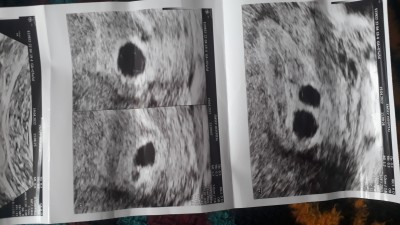

7+4 kese var ama kesenin içi boş bi hafta sonra gel dedi doktor yoksa kürtaj dedi,benim gibi olupta sonradan kalp atışı duyan var mı?

Gebelik haftası 7+4

Canım bide 2 kese var ikiz oldugu icin bebekler normalden daha kucuk olabilirler o yuzden de gozukmemis olabilir